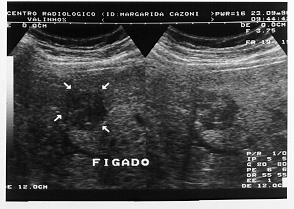

Tomografia computadorizada de abdome(imagem 1 e imagem 2)

No pós-operatório foi submetida a radioterapia adjuvante no retroperitôneo. Evoluiu bem, sem evidência de recidiva durante o segmento ambulatorial até setembro de 1996, quando o ultrassom abdominal mostrou metástase hepática isolada (imagem 3), confirmada pela Tomografia computadorizada.